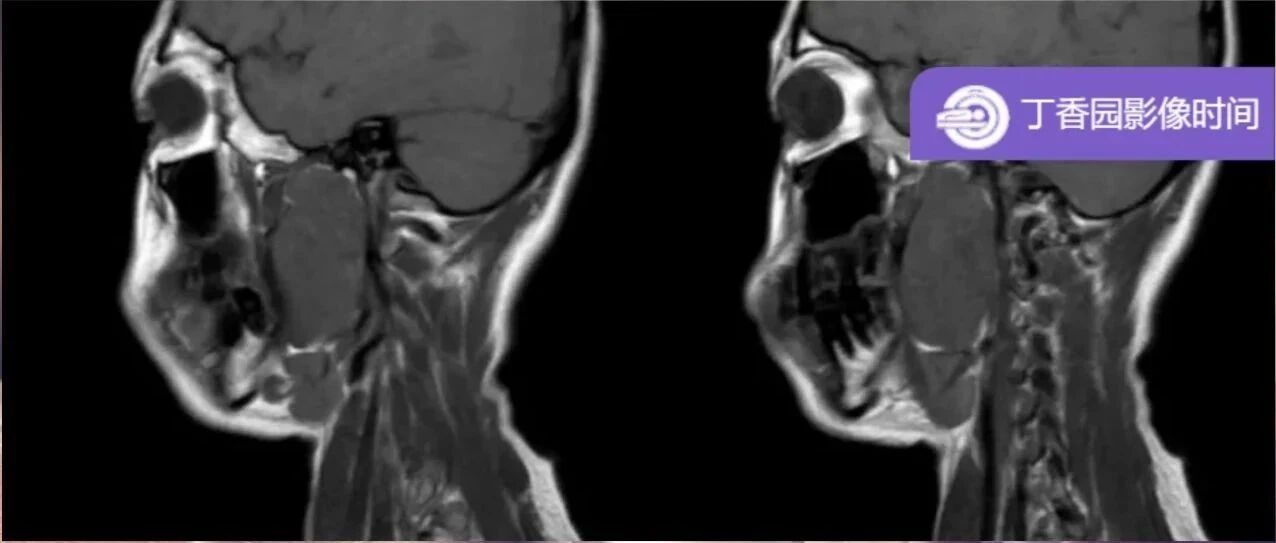

让你过目不忘的颈动脉体瘤 丁香园影像时间 · 公众号 · 医学 · 1 年前 · |